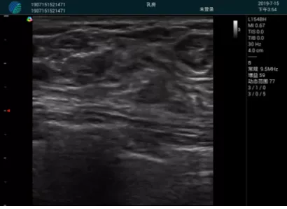

甲狀腺囊性結(jié)節(jié),囊壁鈣化,透聲好

甲狀腺囊性占位